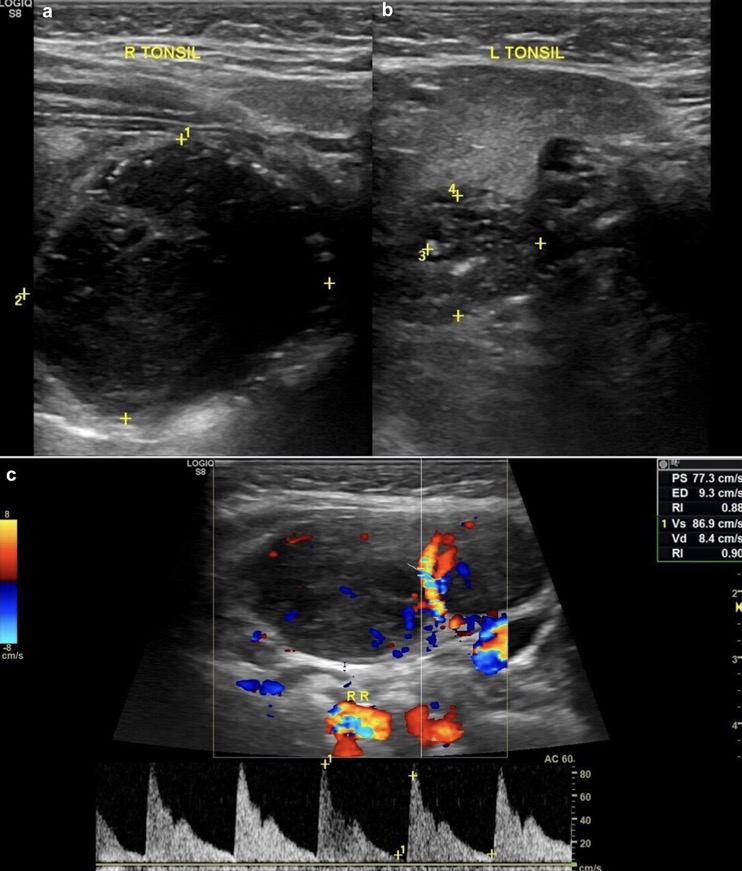

1. Asymétrie de la taille des amygdales (élargissement unilatéral)

2. Sphérique au lieu d'ovoïde

3. Altération de l'échotexture des amygdales

(A) Homogènement hypoéchogène

(B) Perte de son apparence striée

4. Augmentation de la vascularisation amygdalienne interne

EX: LYMPHOME DE BURKITT